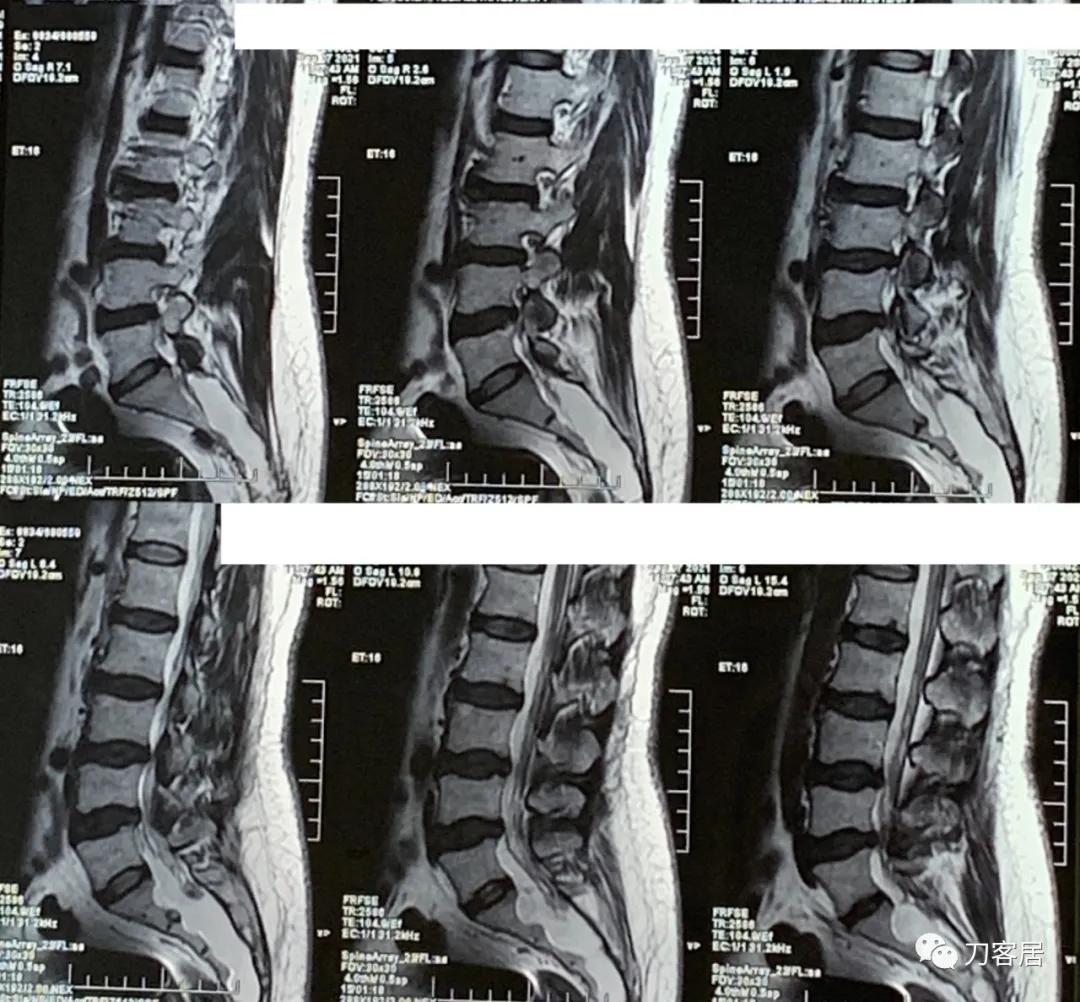

图2. 20210907西安国际医学中心腰椎MRI矢状面T2相扫描,提示腰3-4,腰4-5椎间盘突出,椎管狭窄,但似乎没那么严重,骶管囊肿,范围较大。从骶1以远都可看到。

图3. 20210907西安国际医学中心腰椎MRI矢状面T2相扫描,提示腰3-4,腰4-5椎间盘突出,椎管狭窄,但似乎没那么严重,骶管囊肿,范围较大。从骶1以远都可看到。